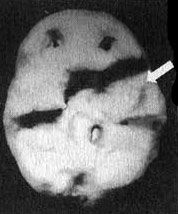

Отсутствие активности в левой височной доле у Эндрю

Трехмерное изображение нижней поверхности мозга

Нормальный мозг

Мозг Эндрю - левой височной доли не видно

Вместе с Эндрю я отправился в отделение сканирования и, пока проводилось исследование, держал его за руку. Эндрю усадили в кресло, в вену ввели иглу, а через нее - малую дозу радиоизотопов. В это время Эндрю играл на ноутбуке в игру на концентрацию внимания. Через несколько минут иглу вынули, и он пошел в соседний кабинет, где делались снимки. Там его уложили на спину на специальный стол. В течение пятнадцати минут камера, медленно двигавшаяся по окружности вокруг головы Эндрю, производила съемку его мозга. Когда изображение было выведено на экран монитора, я подумал, что в ходе исследования была допущена какая-то ошибка. У Эндрю отсутствовала левая височная доля. Просмотрев все снимки, я убедился, что качество сканирования - хорошее. У него на самом деле не было левой височной доли. Что у него было? Киста? Опухоль? Инсульт? Рассматривая эти снимки на мониторе, я испытывал за него сильный страх. В то же время я чувствовал облегчение от того, что мы установили причину его агрессивности. В своих исследованиях и я, и мои коллеги установили связь между нарушениями в левой височной доле и агрессивностью. На следующий день на магнитно-резонансной томографии мы обнаружили у Эндрю на том месте, где обычно находится левая височная доля, кисту (мешок, заполненный жидкостью), размером с мячик для гольфа. Я знал, что эту кисту надо убрать. Однако поиск специалиста, который серьезно отнесся бы к нашим выводам, оказался трудным.